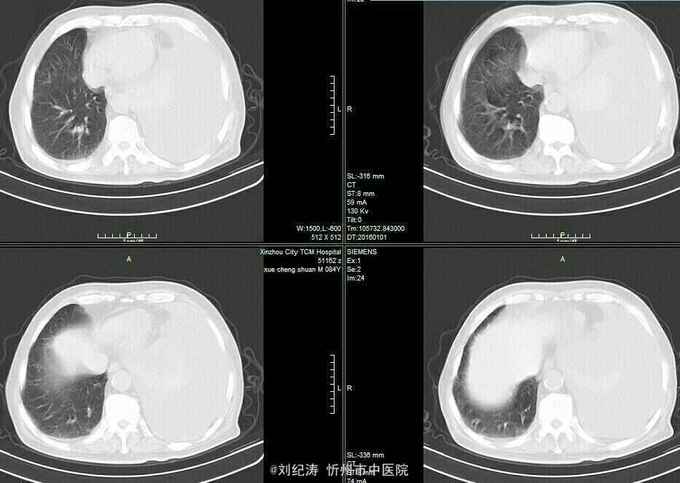

查体:ECOG评分:3分,生命指征平稳,浅表淋巴结未触及明显肿大,双眼睑无水肿,唇无发绀,颈软,双侧胸廓对称,左肺语颤增强,左肺呼吸音消失,右肺呼吸音粗,可闻及哮鸣音,心律齐,腹平软,肝脾肋下未触及,移动性浊音阴性,肠鸣音3次/分,双下肢无水肿。 辅助检查:血常规(2016.1.1):WBC:10.6*109/L,RBC:4.69*1012/L, PLT:165*109/L ,HGB:167g/L.生化(2016.1.1):谷丙转氨酶11U/L,谷草转氨酶11U/L,总蛋白60g/L,白蛋白33g/L,尿素:9.8mmol/L,肌酐:123umol/L,尿酸:251 umol/L,血糖:7.37 mmol/L;电解质:钾:4.79mmol/L,钠:123.5 mmol/L,氯:85.7 mmol/L,钙:2.03 mmol/L。肺部CT(2016.1.1):左肺完全萎缩,左侧胸腔大量积液,右肺未见异常,纵膈轻度右移,未见明显肿大淋巴结。